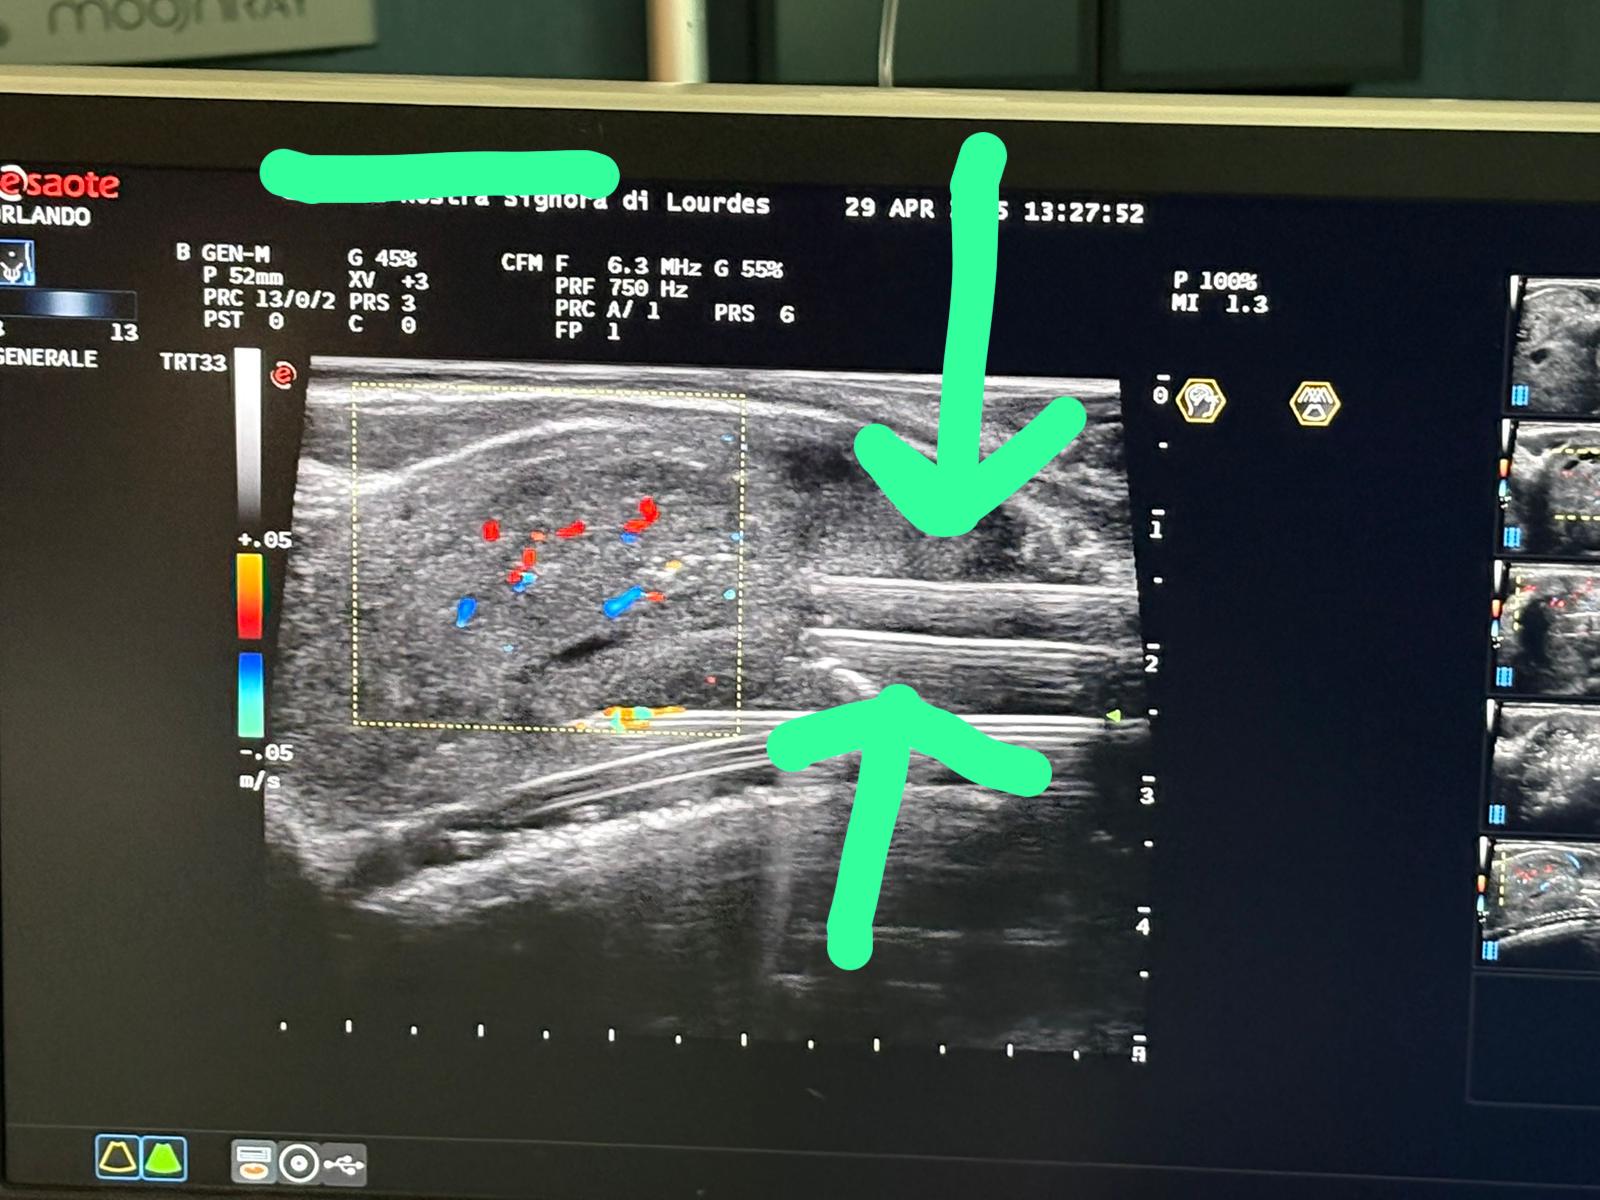

TPLA - Terapia Termica Laser Percutanea Ecoguidata

Innovativa tecnica percutanea sotto guida ecografica. Esegue una necrosi controllata della porzione centrale della prostata. Indicato per prostate anche voluminose. Non necessita di resezione né cateterismo prolungato.